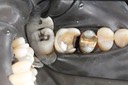

Gary Umeda #3 - 4 prep